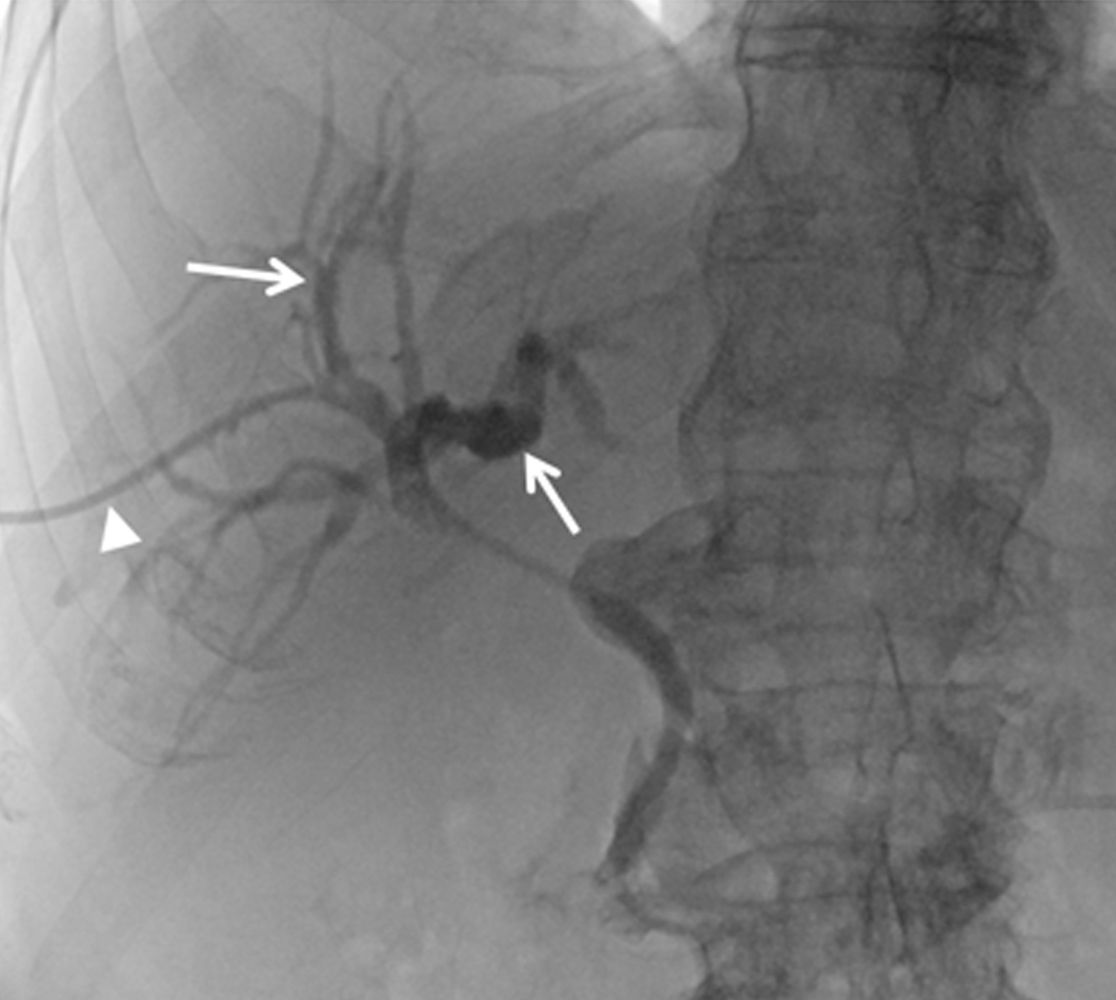

Darstellung der Gallenwege (Pfeile) über die einliegende Drainage (Pfeilkopf) in der Angiographie.